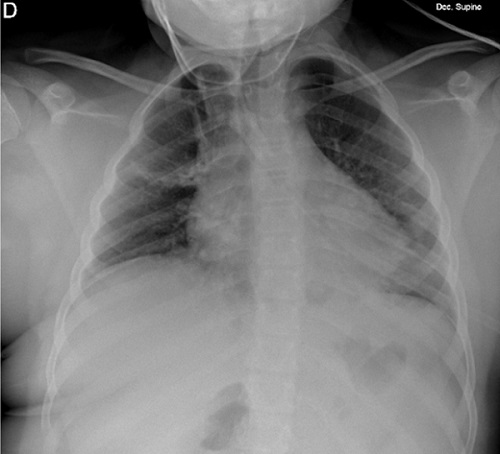

En la analítica sanguínea destaca: leucocitos: 9100/µL (neutrófilos: 7400), hemoglobina: 8,8 g/dL, PCR 6,66 mg/dL. La radiografía de tórax muestra atelectasias en lóbulo superior derecho y consolidación en lóbulo inferior izquierdo (Figura 1).

| Figura 1. Radiografía de tórax donde se observan atelectasias subsegmentarias en lóbulo superior derecho y consolidación parenquimatosa en lóbulo inferior izquierdo |